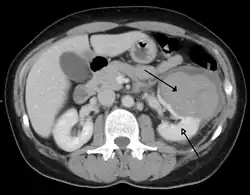

Abdominal trauma resulting in a right kidney contusion (open arrow) and blood surrounding the kidney (closed arrow) as seen on CT

Kidneys

The kidneys may also be injured; they are somewhat but not completely protected by the ribs.[6] Kidney lacerations and contusions may also occur.[13] Kidney injury, a common finding in children with blunt abdominal trauma, may be associated with bloody urine.[13] Kidney lacerations may be associated with urinoma or leakage of urine into the abdomen.[4] A shattered kidney is one with multiple lacerations and an associated fragmentation of the kidney tissue.[4]